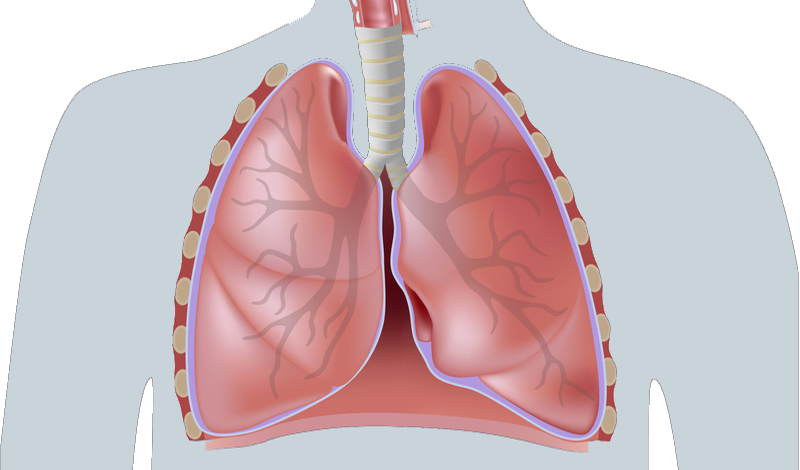

Нижние дыхательные пути: гортань, трахея и легкие (крупные и мелкие бронхи)

Заболевания: острый вирусный бронхит - - - ПЦД